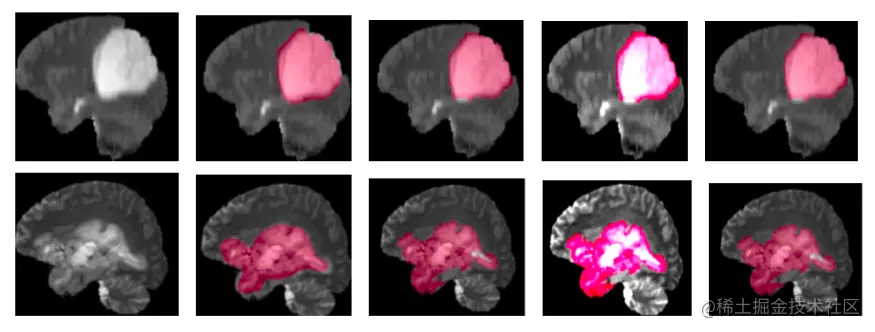

分割所涉及的不确定性如图3所示。深的颜色表示更自信,而浅的颜色表示模型在这些区域不太自信。

图片

图3:与ground truth分割相比,测试样本上的模型预测示例。第一列:输入图像,第二列:真值分割,第三列:预测分割,第四列:随机不确定性,第五列:认知不确定性